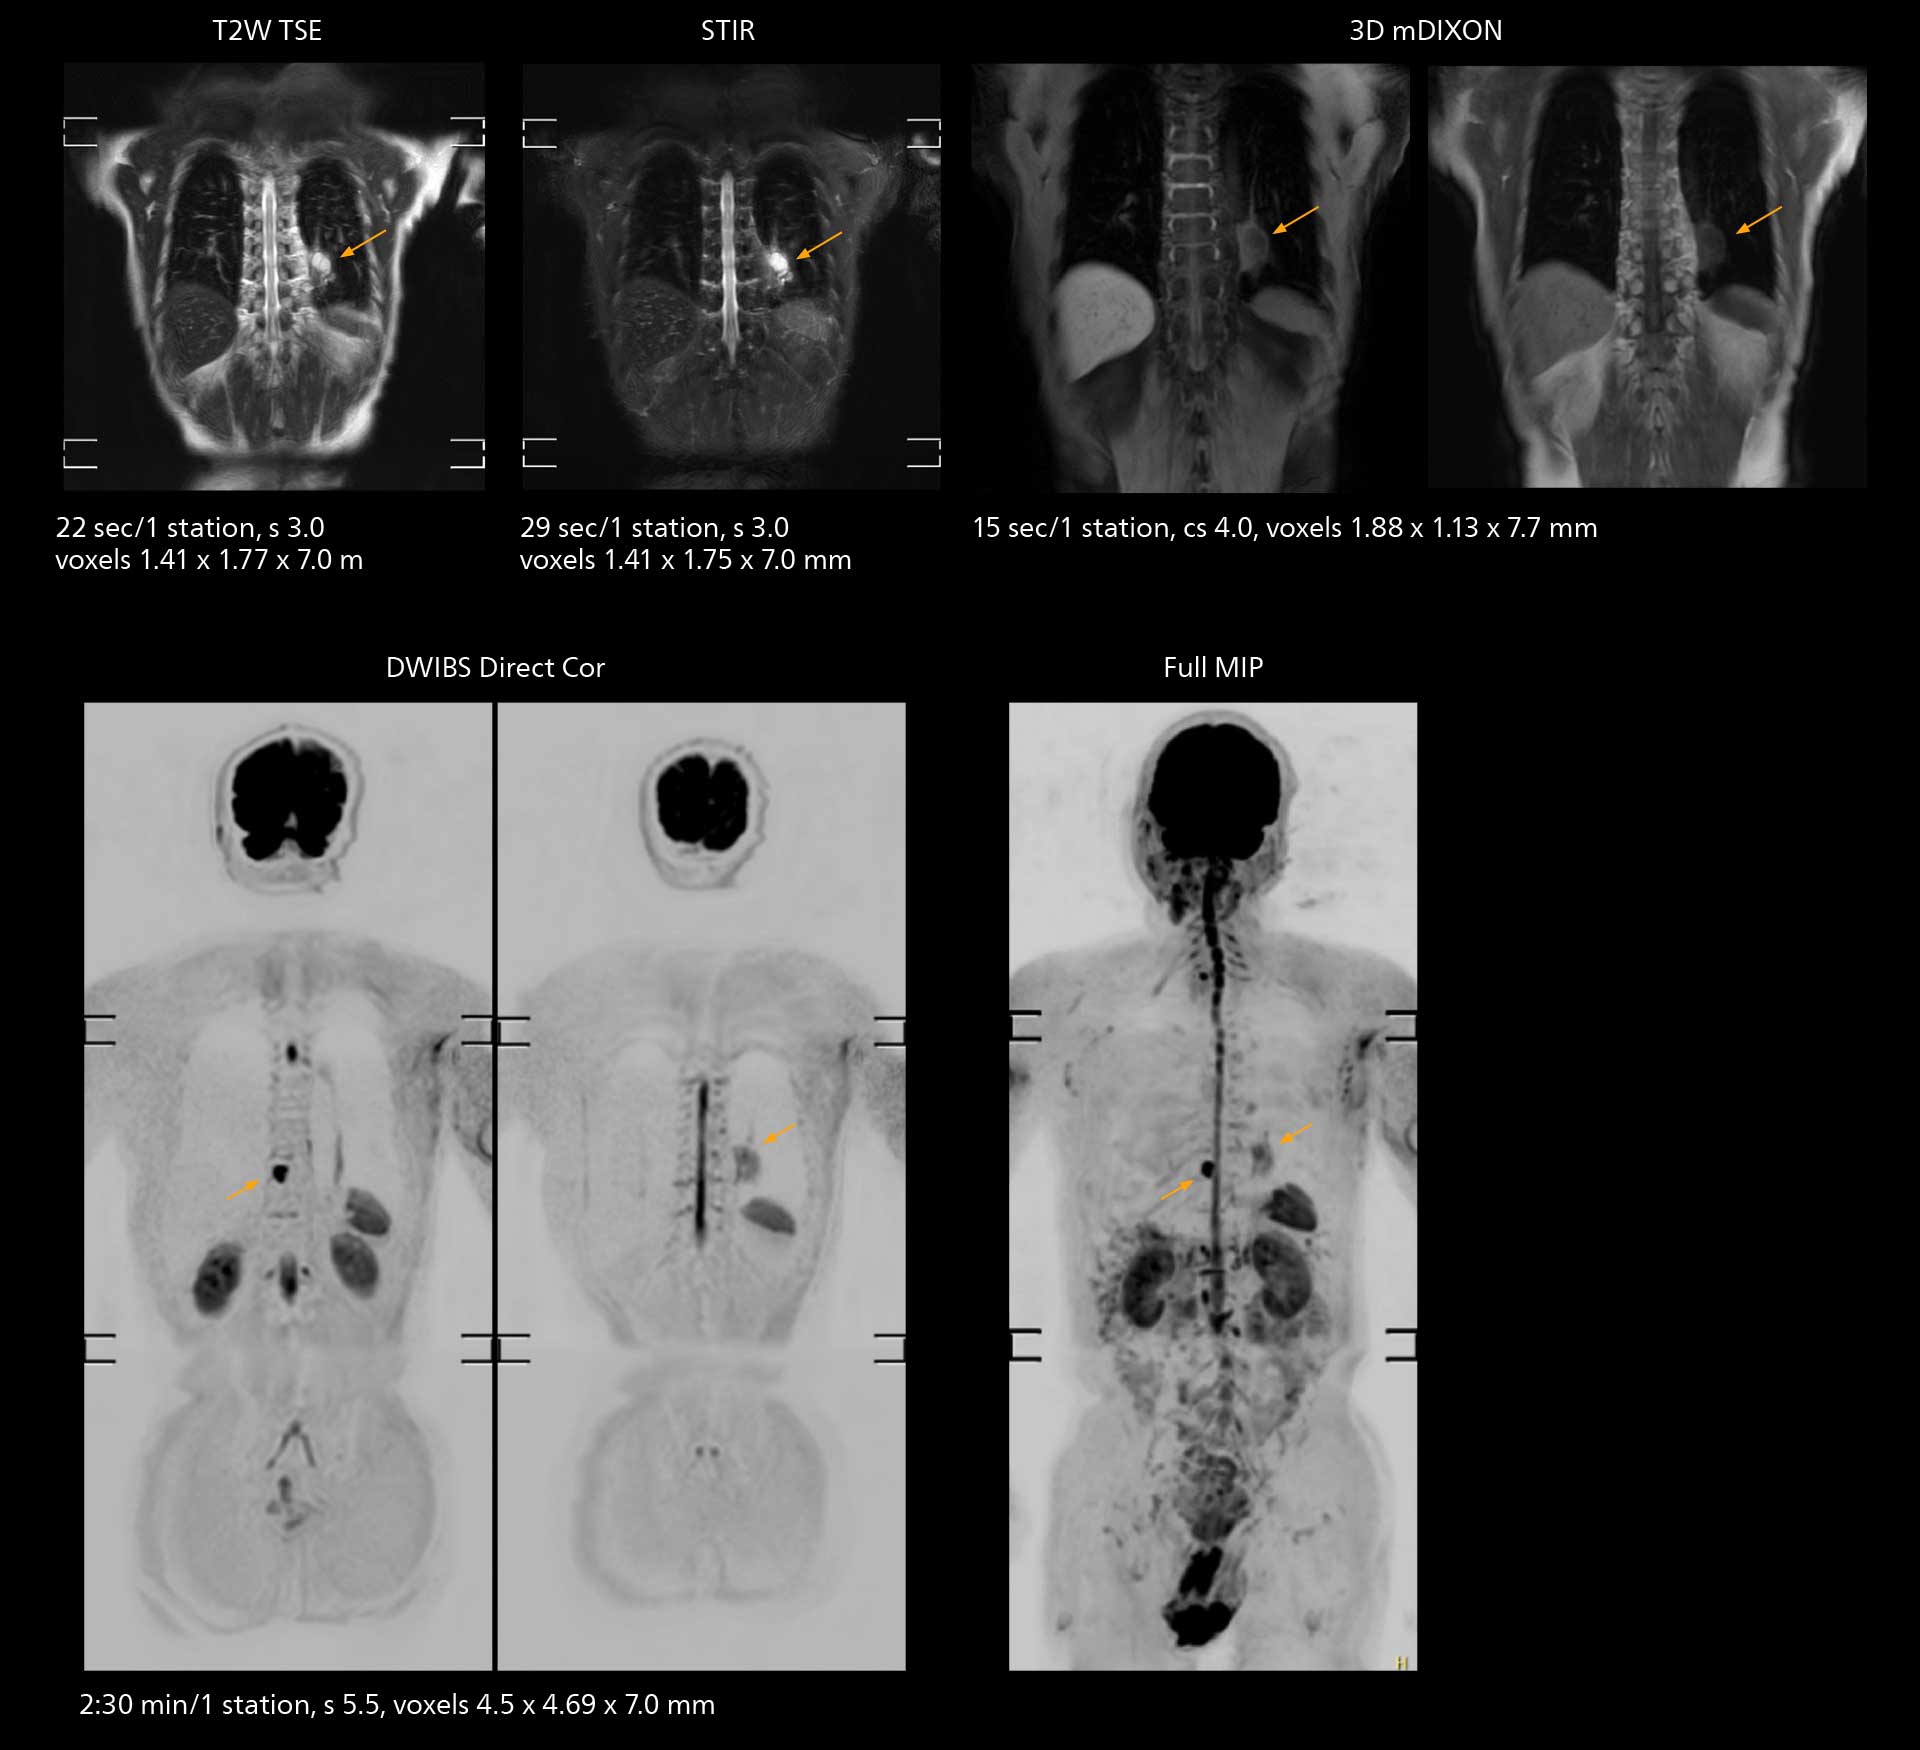

MRI of the knee

Images showing a posterior cruciate ligament (PCL) tear, a detached medial collateral ligament (MCL) on the tibial side and an intact anterior cruciate ligament (ACL). SmartPath to Elition X helped reduce scan time compared to previous imaging while maintaining resolution.

An example of increased imaging speed is in knee studies. “There is a definite scan time reduction for T2* mFFE and proton density TSE – both of these sequences benefit from much shorter repetition times,” he reports.

Overall, imaging time per sequence has been reduced since the Elition X upgrade. This can help reduce the risk of patient movement and the need for rescans.